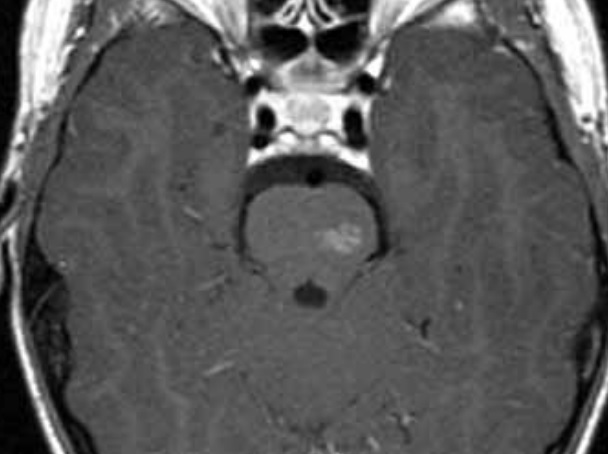

cavernoma

dilated vascular cavity lined by vascular endothelium

typically supratentorial

popcorn appearance on MRI, core can be hyperintense, dark rim on T2

can cause seizures, can bleed